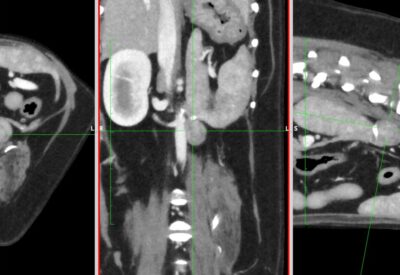

画像検査(エコー検査やCT検査)では確定することはできませんが、褐色細胞腫を疑うことは可能です。

・CT検査:がんの大きさや広がり、リンパ節転移、遠隔転移(肝臓、肺など)の評価

※CT検査はより綿密な治療方針を決定するうえで必須の検査です

褐色細胞腫のCT画像(赤丸:副腎褐色細胞腫、青矢印:動脈)